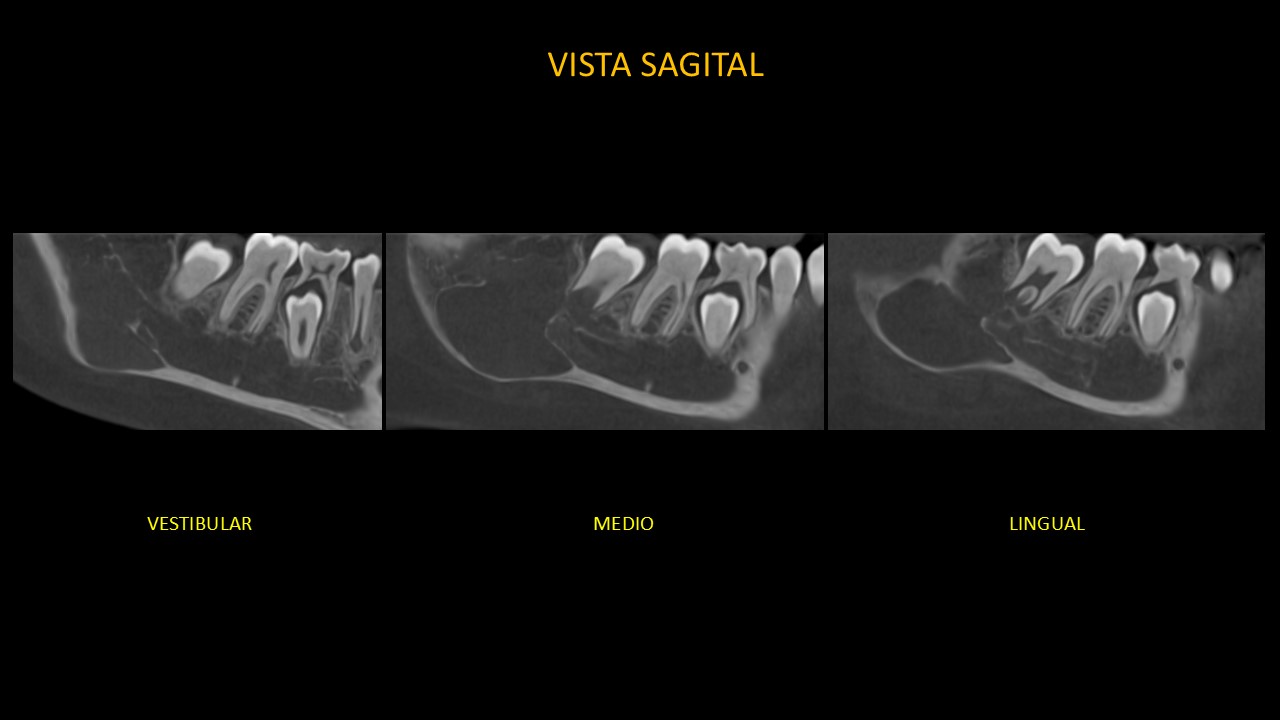

Figura 4

En las vistas sagitales (Figura 4), podemos confirmar el adelgazamiento y la expansión de la basal mandibular ; y su cercanía a la pieza 47.